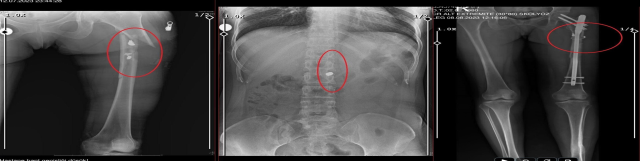

İlyas Sarıkaya, sevgilisi Fatma O.'yu da 8 kurşunla vurup, yaraladı. Arkadaşı Özaslan'ın cesedini önce çarşafa sonra da streç filme sarıp bantlayan Sarıkaya, eczaneden aldığı sargı bezi ve ilaçlarla pansumanını yaptığı sevgilisine yaralı haldeyken 21 gün boyunca cinsel saldırıda bulundu.

Recep Özaslan'ın cesedinin çürümesiyle çıkan koku, komşuları rahatsız edince ihbarla adrese polis ekipleri sevk edildi. Sarıkaya, eve gelen polisleri silah zoruyla tehdit ettiği sevgilisini pencereye çıkarıp sorun olmadığını söyleterek geri gönderdi. Olay, Fatma O.'nun 12 Temmuz'da, Sarıkaya'nın sehpa üzerinde unuttuğu telefondan annesine mesaj yazıp yardım istemesiyle ortaya çıktı.

EKİPLER YARALI KADIN VE KOKMAYA BAŞLAYAN CESEDİ GÖRDÜ

Fatma O.'nun annesi, telefonla aradığı Sarıkaya'yı, kızına para götürmesi için evine çağırdı. Ekipler, parayı almaya gelen Sarıkaya'yı kendilerine silah çekmesine rağmen yakaladı. Eve giden ekipler, ağır yaralı haldeki Fatma O. ve kokmaya başlayan cesetle karşılaştı.